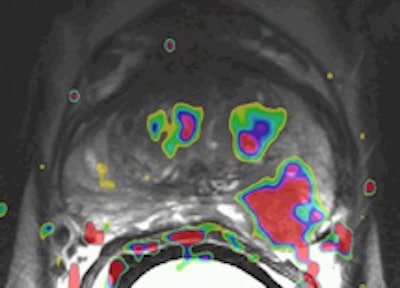

A 69-year-old male three years post electron-beam radiation therapy (EBRT, primary PC: Gleason 4+3 right PZ) with PSA increase to 2. MRI and TRUS-guided biopsy of this area confirmed Gleason 4+4 recurrence at right PZ (old tumor location). Left: Axial T2-weighted MR image shows low signal prostate due to previous EBRT. Therefore, tumor (arrow) is difficult to see. At arrow, there is some "bulging" (PI-RADS 5). Center: Axial DCE-MRI shows increased focal asymmetric contrast leakage at right PZ (circle, PI-RADS 5). Right: Axial ADC-map of DWI-MRI shows restriction (low signal, circle, PI-RADS 5). Final diagnosis: PI-RADS 5. TRUS biopsy of this area confirmed Gleason 4+4 recurrence."Prostate imaging at 3-tesla benefits from higher signal-to-noise ratio and enables high-quality imaging within a short time without the use of an ERC [endorectal coil]. Data on 3-tesla for prostate cancer MRI are still conflicting. Thus, further research on this topic is needed," the authors noted. "Limitations of 3-tesla MRI are shorter T2- and longer T1-relaxation times, problems with susceptibility artifacts, dielectric effect, specific absorption rate, and the homogeneity of the magnetic field. However, hardware, multichannel coil, and parallel imaging technique improvements are currently solving most of these problems."